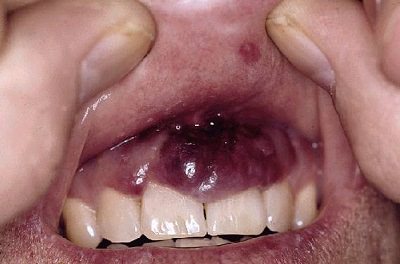

AIDS'li hastalarda en sık görülen sarkomdur. Lezyonlar vücutta daha dağınık ve yaygındır, sıklıkla gövde, baş ve boyunda gözlenir. Mukozal ve iç organ tutulumları da görülebilir.

AIDS ile ilişkili KS'ye "human herpesvirus 8 (HHV-8)" neden olur. Kaposi sarkomu, aynı zamanda mukoza tutulumu da gösterebilen bir hastalıktır.